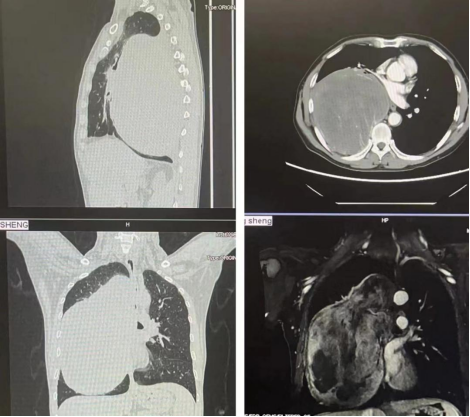

患者为54岁男性,反复头晕,伴胸部隐痛及气喘1+月,于2023年10月前往华西天府医院内分泌科就诊,入院后诊断严重低血糖,完善胸部CT后提示:右侧胸腔巨大软组织肿块影,大小约30cm×20cm×15cm,与后胸壁、右肺及纵隔分界欠清,增强扫描可见明显不均匀强化,内见多发小血管影,纵隔受压左偏,气管下段、右肺主支气管及其分支、左肺主支气管近端受压狭窄,右肺受压不张,右肺动静脉受压变窄。穿刺后病理提示:梭形细胞肿瘤;免疫组化染色结合形态学支持孤立性纤维性肿瘤。

术前影像学图像